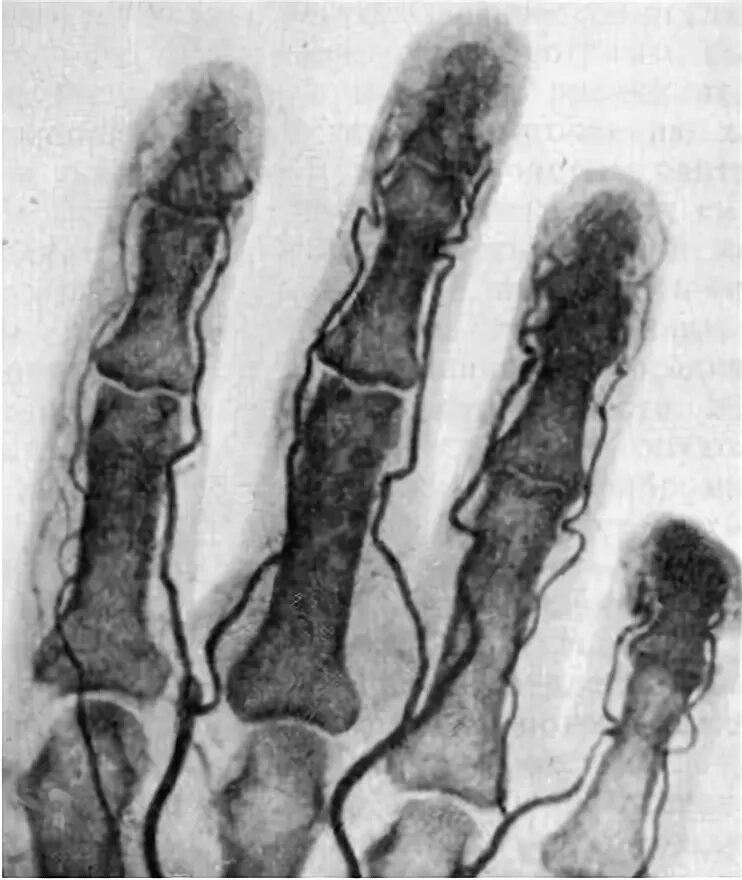

Синовиомы